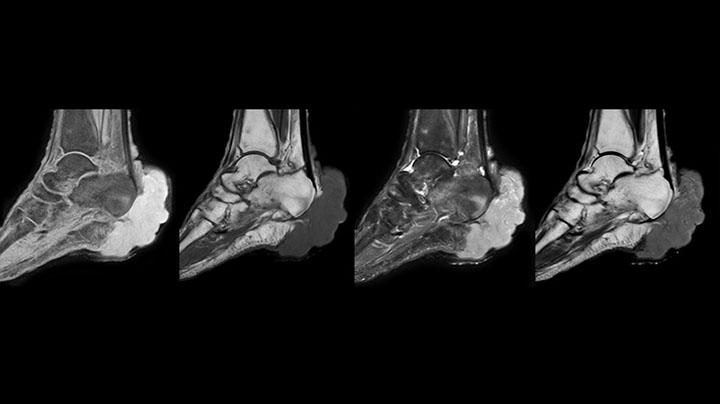

MRI examination on Prodiva 1.5T of a 72-year-old female with a malignant melanoma in the ankle. mDIXON TSE provides excellent fat suppression, without the distortion that is often seen at such extremities.

Scan time 2:55 min, FOV 160 mm, acq voxels 0.55 x 0.83 x 3.0 mm.

Scan time 4:19 min, FOV 160 mm, acq voxels 0.55 x 0.80 x 3.0 mm.

Scan time 2:50 min, FOV 160 mm, acq voxels 0.70 x 0.99 x 3.0 mm.